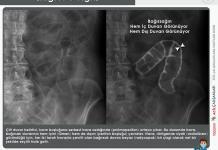

Pozisyon : Çekim ayakta ve P-A (Arka-Ön) pozisyonunda yapılmalıdır. Hastanın karnı statife değmelidir. Konvansiyonel röntgen kullanılıyorsa kasetin, dijital röntgen kullanılıyorsa dedektörün ortası iliak çıkıntının ( krista iliakanın ) 5cm kadar üstüne gelmelidir.

Santralizasyon ve Tüp Açısı : Diyafram kubbelerinide kesmeyecek ölçüde kaset (35X43) veya dedektör seçimi yapılmalıdır. Tüp kaset mesafesi 100 cm olmalıdır. Santralizasyon iliak kanadın 5 cm üzerine filme dik olacak şekilde yapılmalıdır. Hasta pozisyonu ayarlanıp gerekli ölçülerde kolimasyon yapıldıktan sonra grafi alınırken hastaya solunumu derin inspiryum sonunda tutturularak diyafragmanın aşağı inmesi sağlanır. Tetkik sırasında ekspojur zamanı kısa tutulmalıdır. Ortalama bir erişkin için 100 KV ve otomatik MaS ile çekim yapılabilir.

Serbest intraperitoneal havayı saptamak için en kullanışlı pozisyon sol lateral dekübit pozisyonudur.